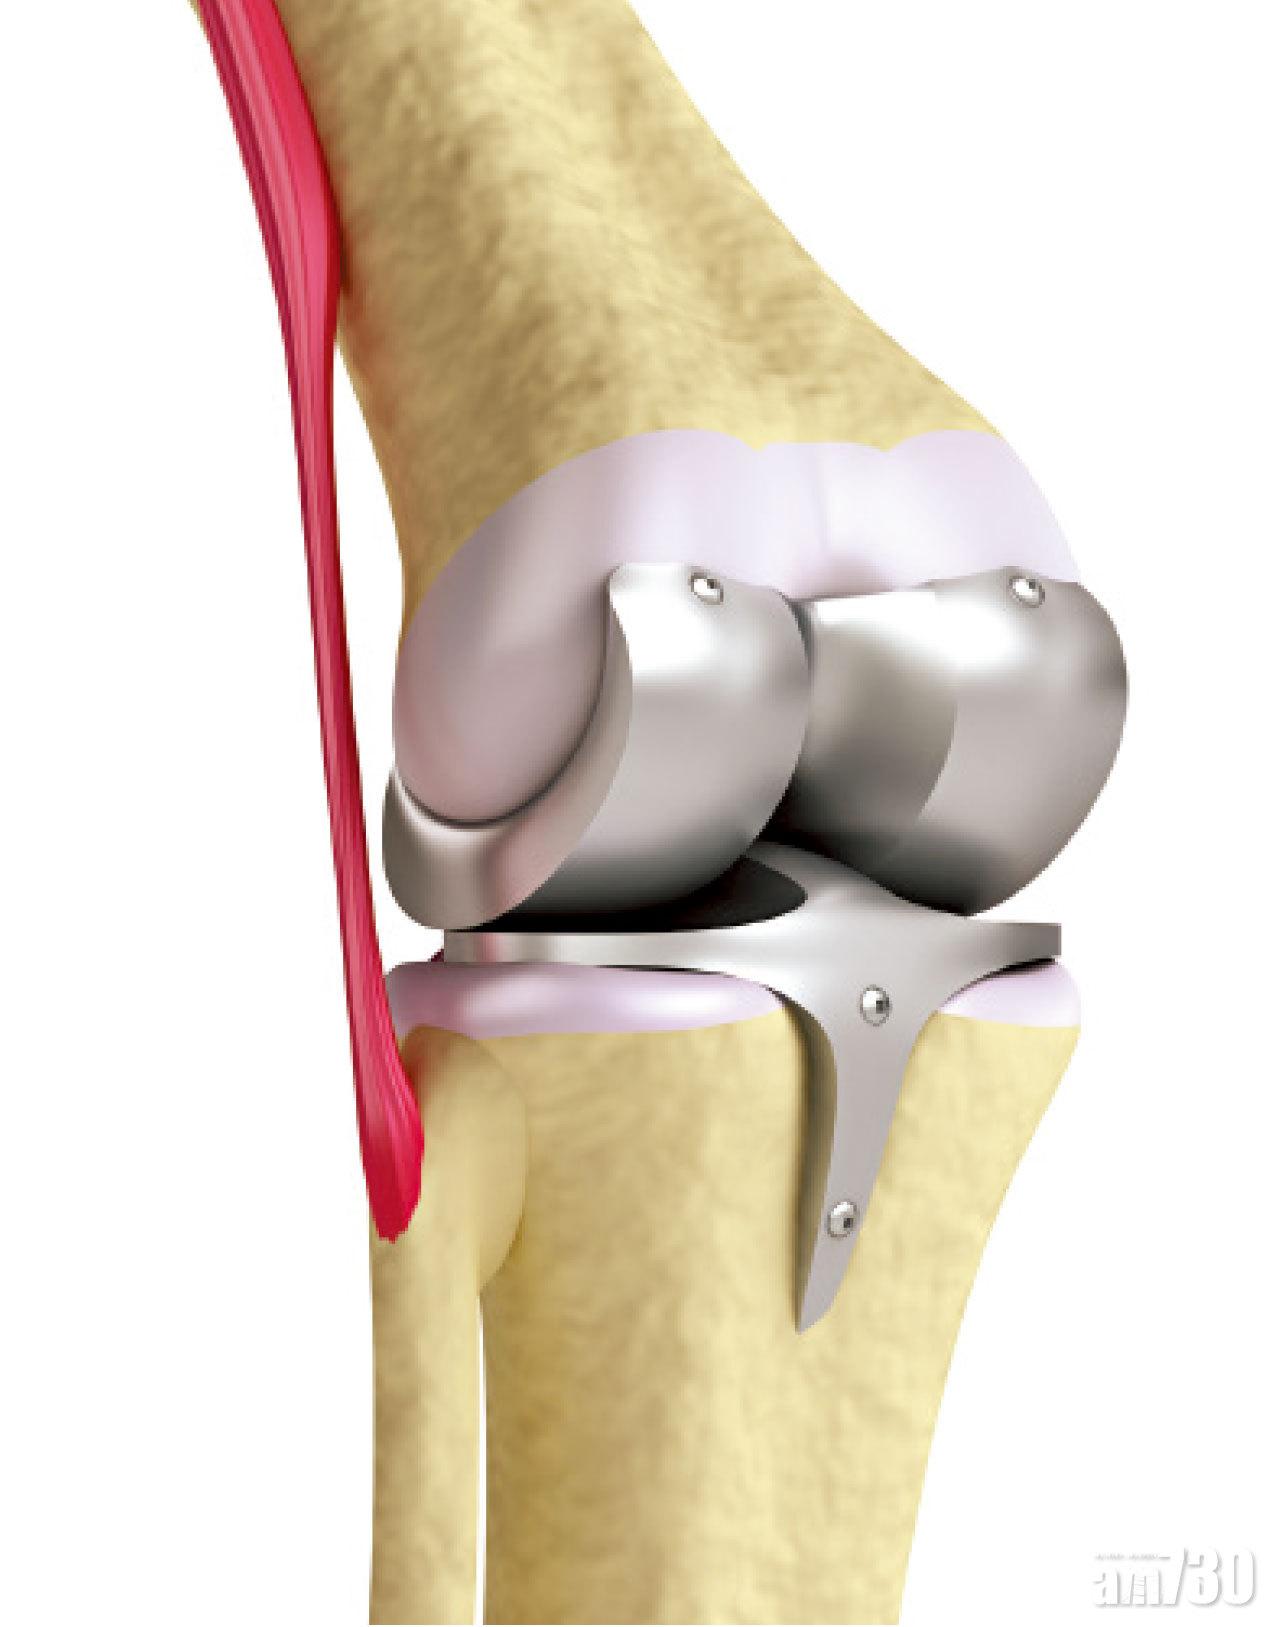

情況較嚴重者就要接受手術治療。手術分為三種,包括關節鏡下清洗關節、高位脛骨截骨術及人工關節置換。5年前開始,香港大學團隊引入快速康復關節置換模式,手術時間由以前的2至3小時,縮短至半至1小時。患者於術後當日或翌日,即可走動。部分人的退化只集中在部分關節,可考慮作半膝關節置換,保留未退化那一邊的關節,有助降低創傷程度及流血量。術後關節愈合會較自然,康復速度也較快。

部分患者抗拒更換關節的原因,是覺得需要每10年更換一次,那倒不如年紀再大些才更換。其實,現時的人工關節因物料的改善,耐用度比昔日的為佳,超過九成人工關節可使用10年,而超過八成人工關節壽命可達20年。因此,是否更換人工關節,不是根據年齡,而應視乎患者關節的退化嚴重程度,以及痛楚對生活造成的困擾而決定。